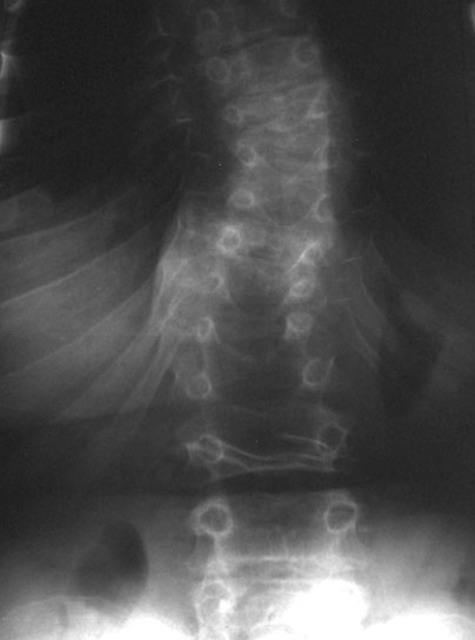

Fig.3. Radiografia frontal da coluna vertebral demonstra platispondilia e escoliose. Créditos: Sciencedirect